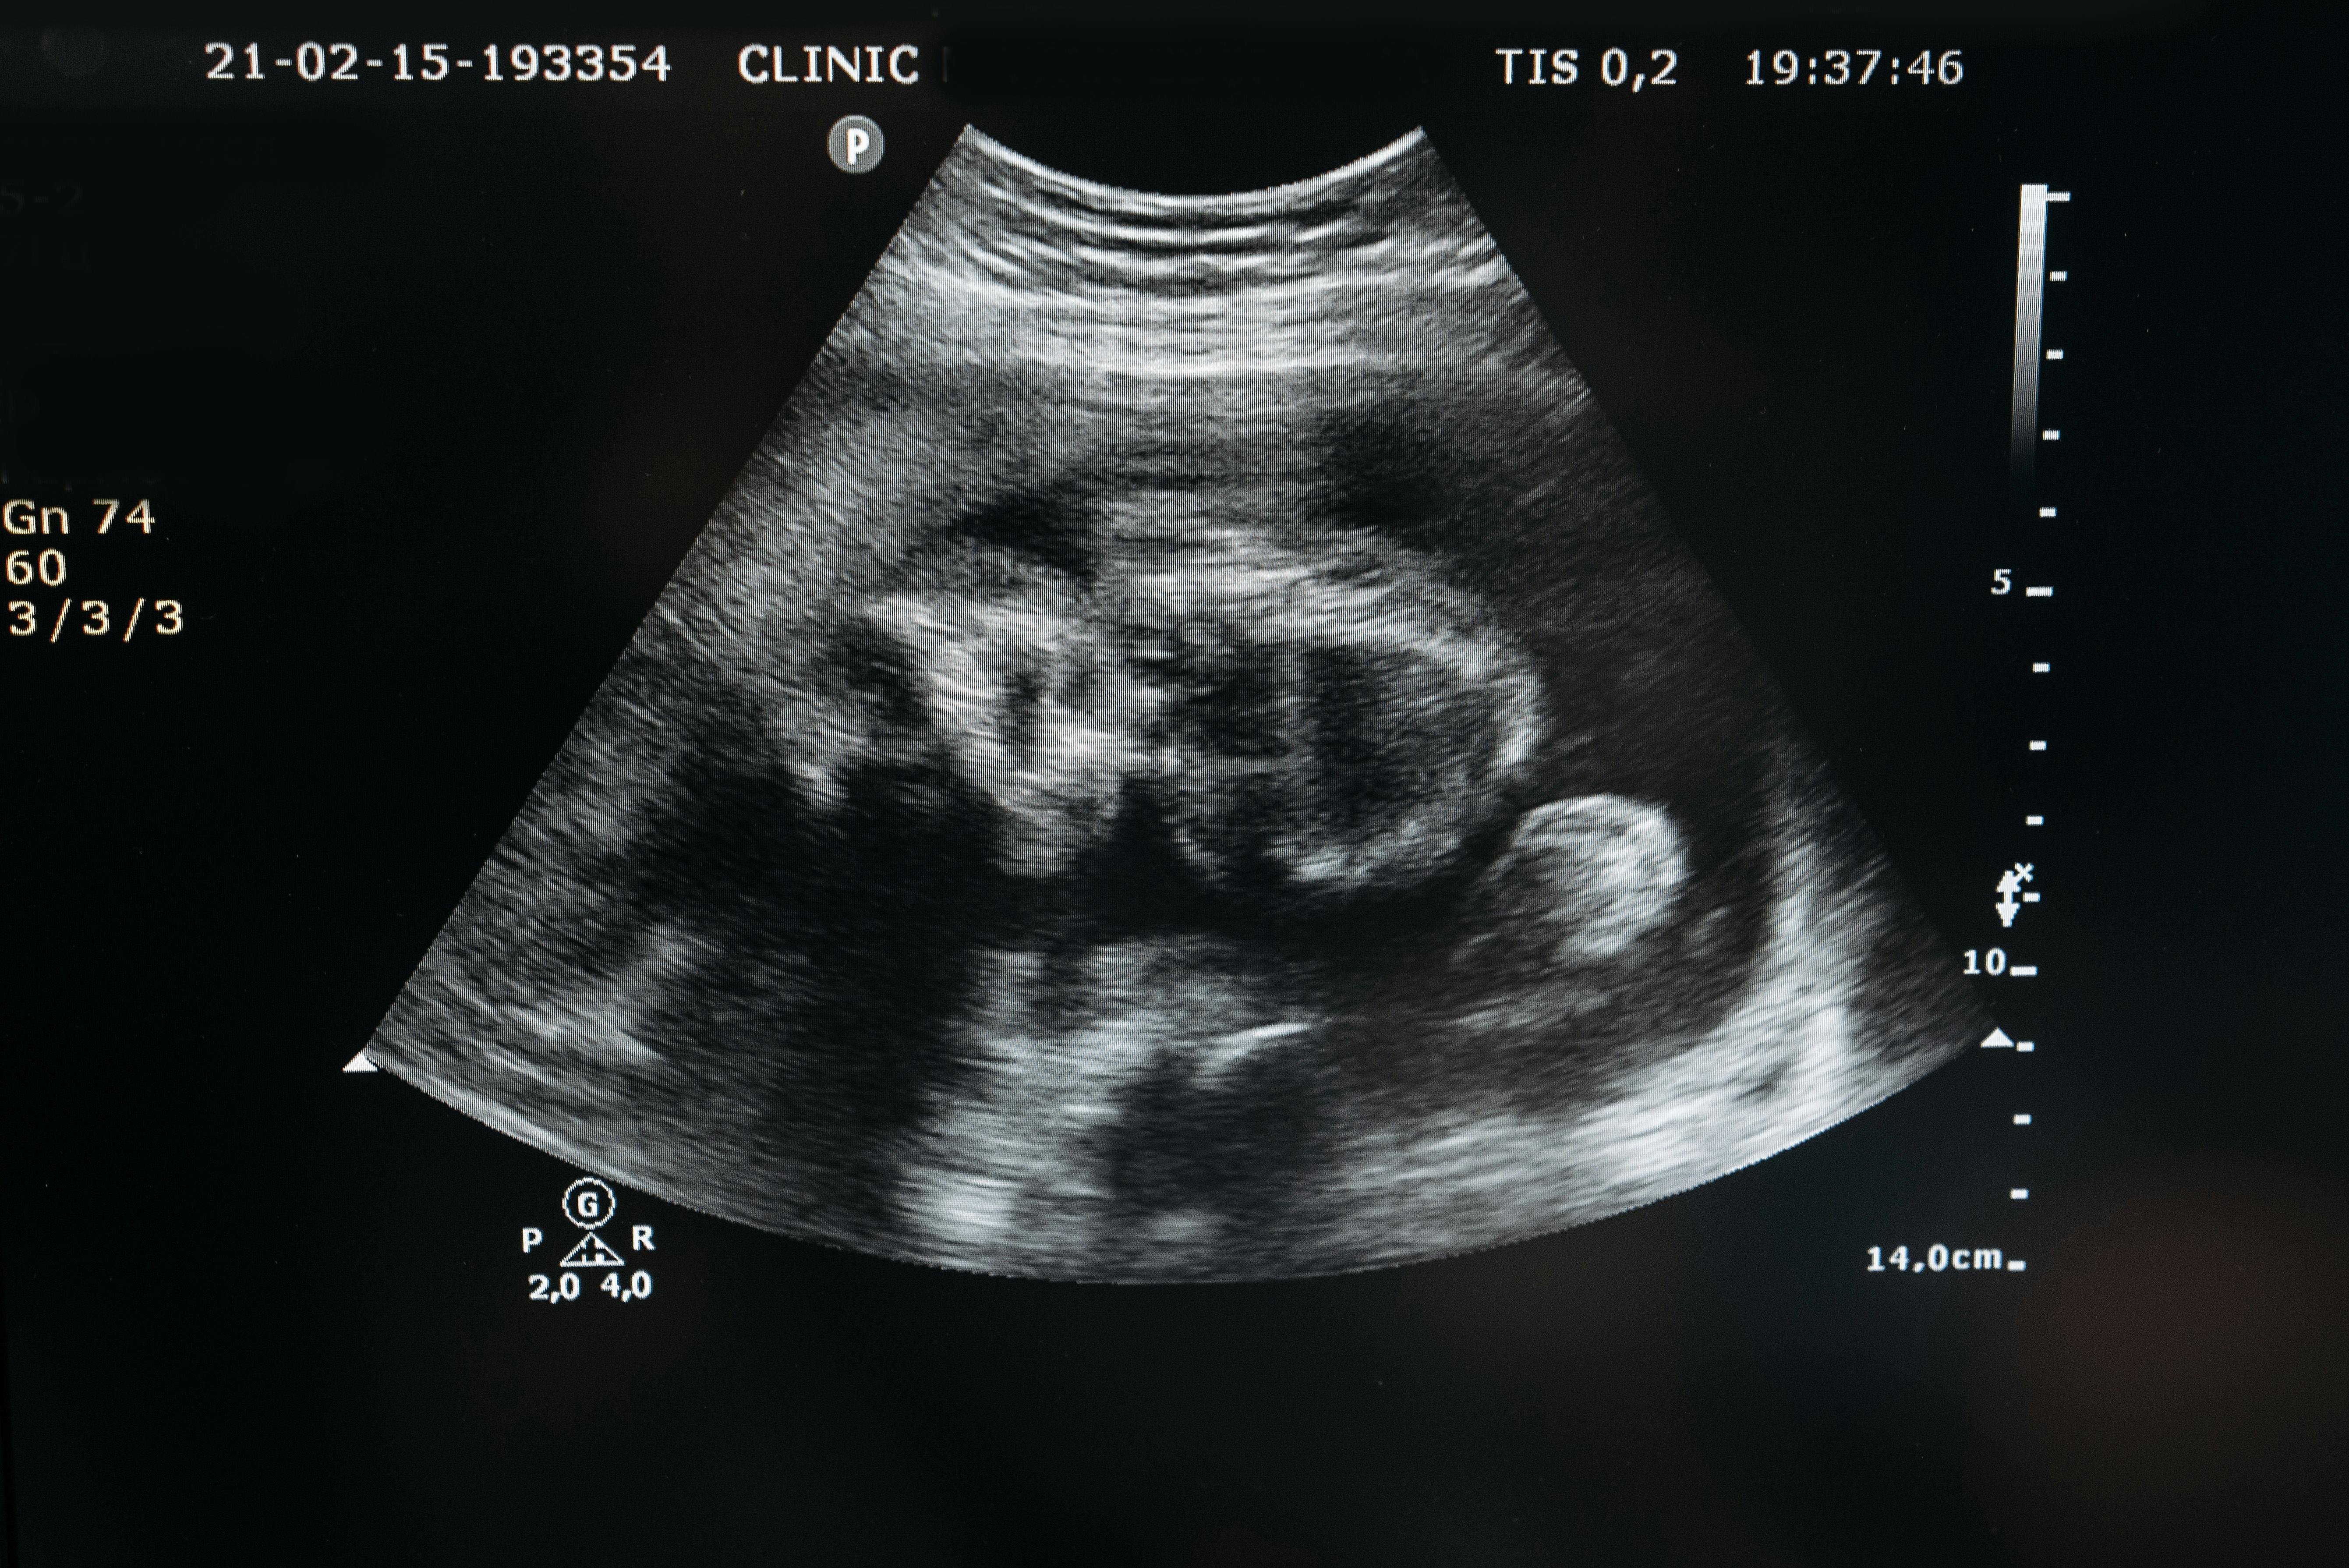

3. 건강검진 결과 전 가입이 유리

산전 검사(정밀초음파 등)에서 이상이 발견되기 전에 가입해야 특약 가입 제한 없이 폭넓은 보장이 가능합니다.